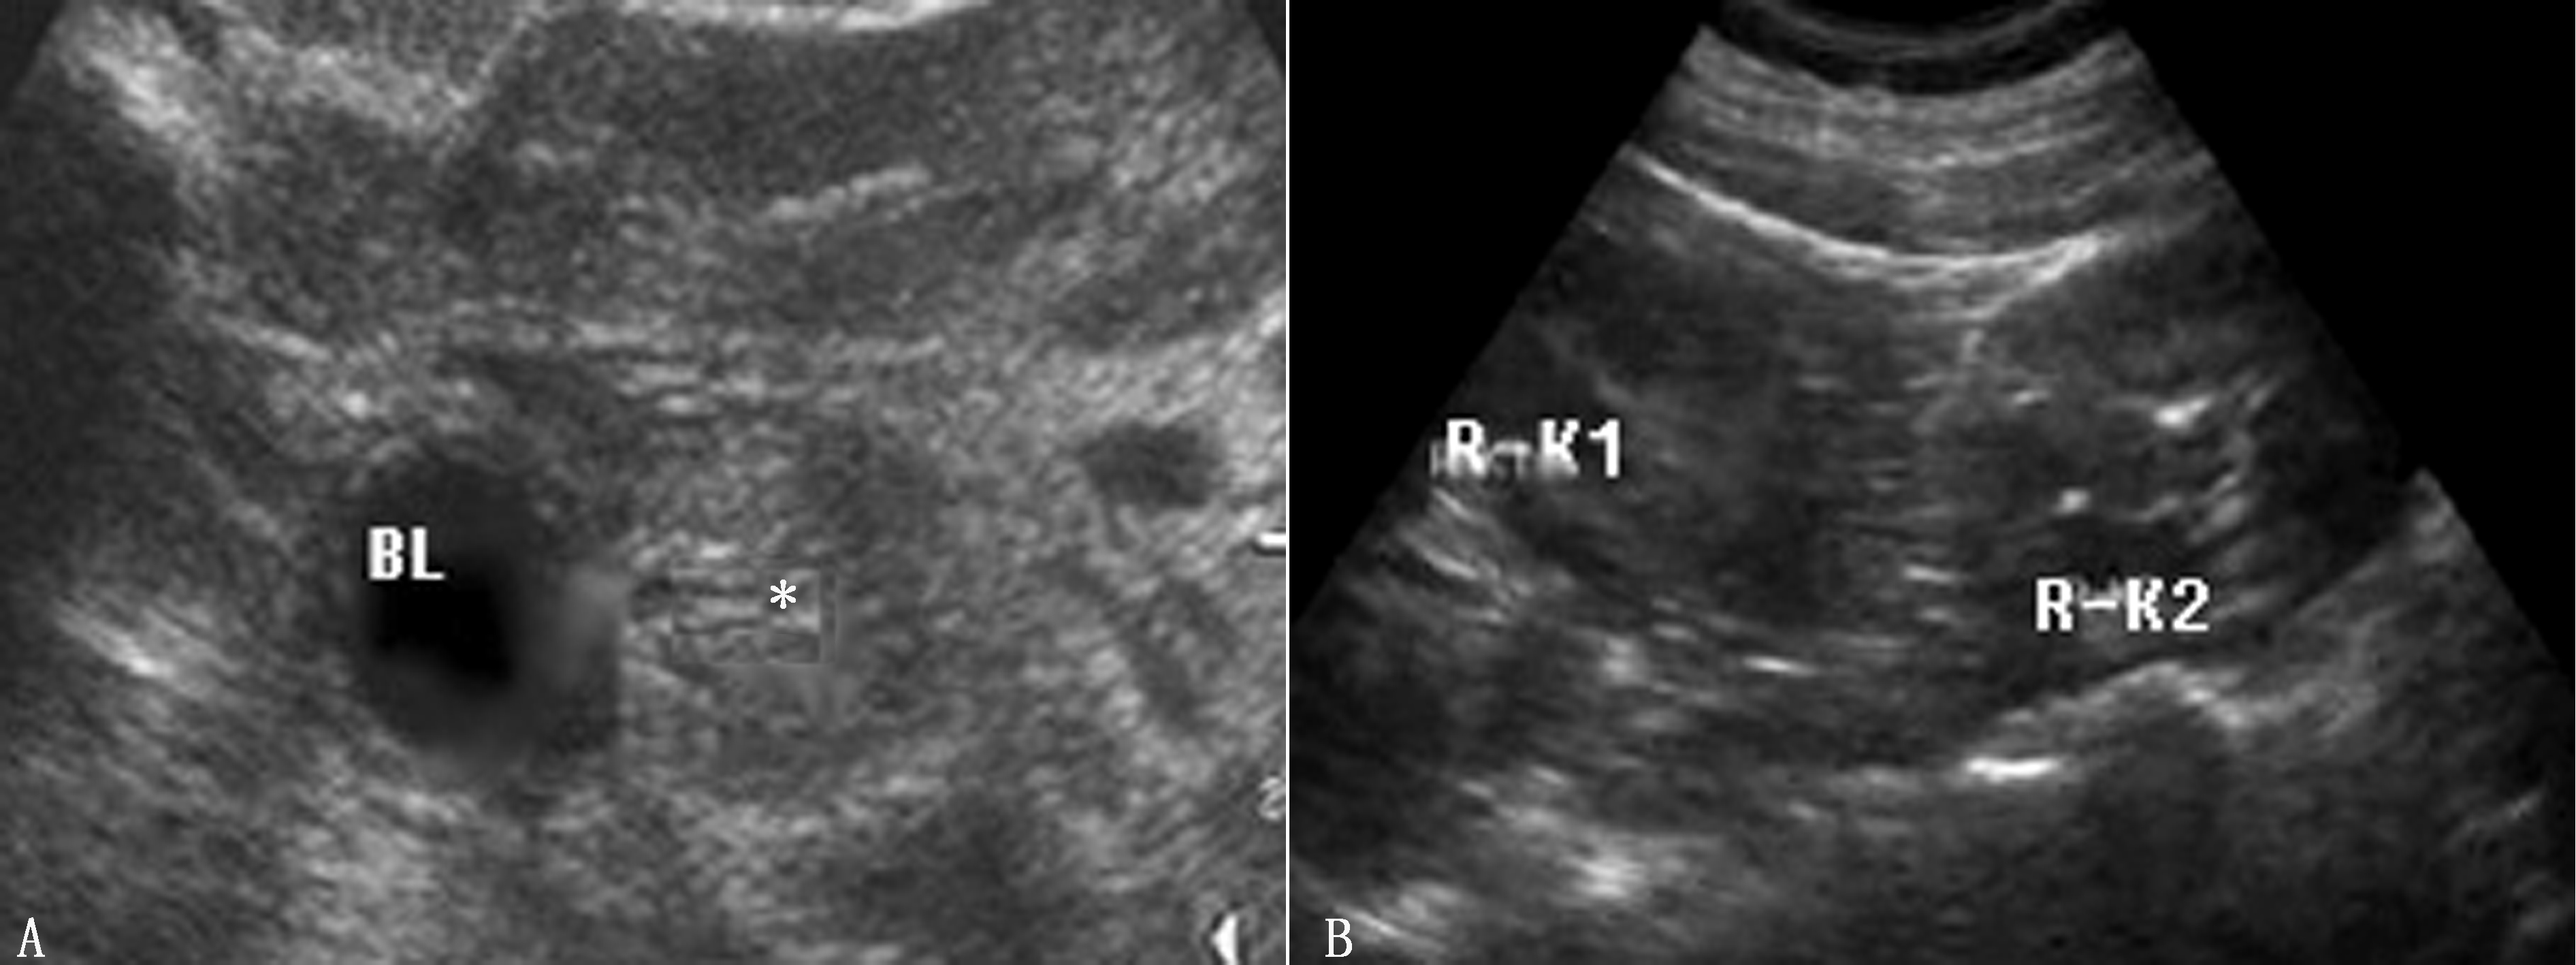

单侧肾缺如又称孤立肾。由于有对侧发育正常的肾脏而不出现羊水过少,胎儿膀胱亦可显示良好,发育正常的肾脏呈代偿性增大。肾脏缺如的一侧超声不能显示肾脏图像,但可显示肾上腺“平卧”征,彩色多普勒可显示该侧肾动脉缺如,而健侧肾动脉存在(图1)。诊断单侧肾缺如时,应特别仔细检查腹内尤其是盆腔内有无异位肾存在,在除外异位肾的情况下才能诊断单侧肾缺如。

图1 孕28周,胎儿一侧肾缺如,肾动脉血流未显示